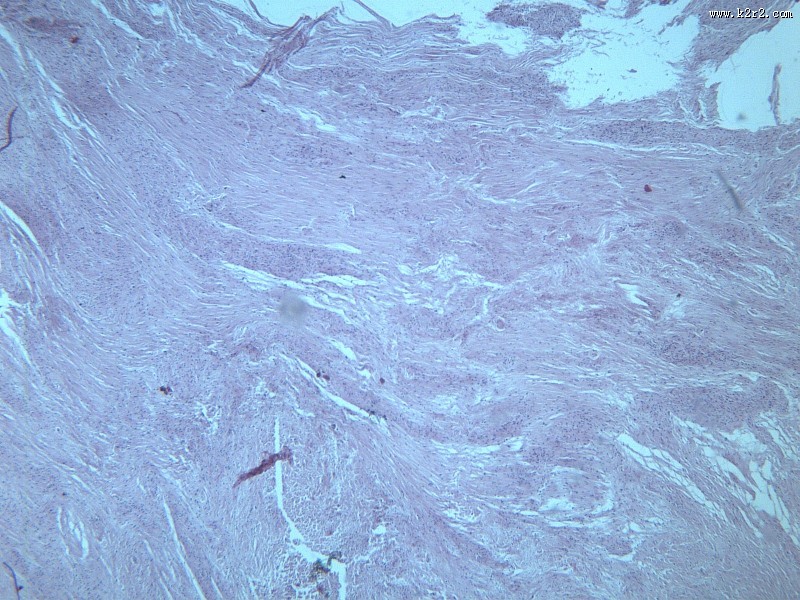

纤维瘤大全 - 第3张

纤维瘤大全

乳腺纤维腺瘤

纤维肉瘤大全

医学

显微切片

肿瘤

fibroma

纤维瘤